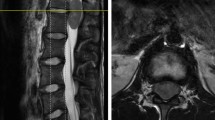

Over the past decade, MRI-guided brain tumor surgery has sought to enhance extent of tumor resection, quality of life, and patient survival. iMRI technology started with 0.5 Tesla systems, but the field has since evolved with 3 Tesla machines currently in use. Several studies have attempted to quantify iMRI effect on extent of tumor resection, but only a few address how iMRI affected the surgical plan, survival, and quality of life.

The main rationale for the use of iMRI over conventional neuro-navigation-guided resection is the avoidance of brain shift related to resected tumor, loss of cerebrospinal fluid, and tissue edema. Conventional neuro-navigation becomes progressively less reliable during surgery, while iMRI can be updated during surgery. Several studies have attempted to quantify the added value of iMRI in brain tumor surgery [110–120]. It has been used with success in surgery for low-grade gliomas, increasing both extent of resection and survival [12, 119, 121]. Schneider et al [119] studied 12 patients with low-grade gliomas who underwent surgery within a 0.5 Tesla iMRI suite. At the point in which the surgeon would have classically terminated the operation as well at the final end of the case, residual tumor was measured using iMRI. The initial extent of resection was 68 %. However, at final analysis, gross total resection was seen in 50 % of cases, 90 % resection in 42 % of cases, and less than 85 % resection in 8 % of cases. Claus et al [12] preformed a single-institution retrospective analysis of 156 patients with unifocal supratentorial low-grade gliomas using iMRI. They noted decreased death rates at 1, 2, and 5 years (1.9 %, 3.6 %, 17.6 %, respectively) compared with historical controls. Given concern that iMRI might lead to an increased rate of postoperative neurological deficits, Nimsky et al [115] reviewed their experience and found no difference.

iMRI for high-grade glioma has been shown to be more effective than conventional neuro-navigation-guided surgery for increasing extent of resection; however, studies examining survival, neurological outcome, and quality of life are limited. Published reports display an overall survival for glioblastoma patients of 13.3–18.5 months for gross total resection and 7.9–11.5 months for subtotal resection using iMRI [113, 120, 122, 123]. As with all surgical modalities, extent of glioma resection must be measured against quality of life and postoperative clinical performance.